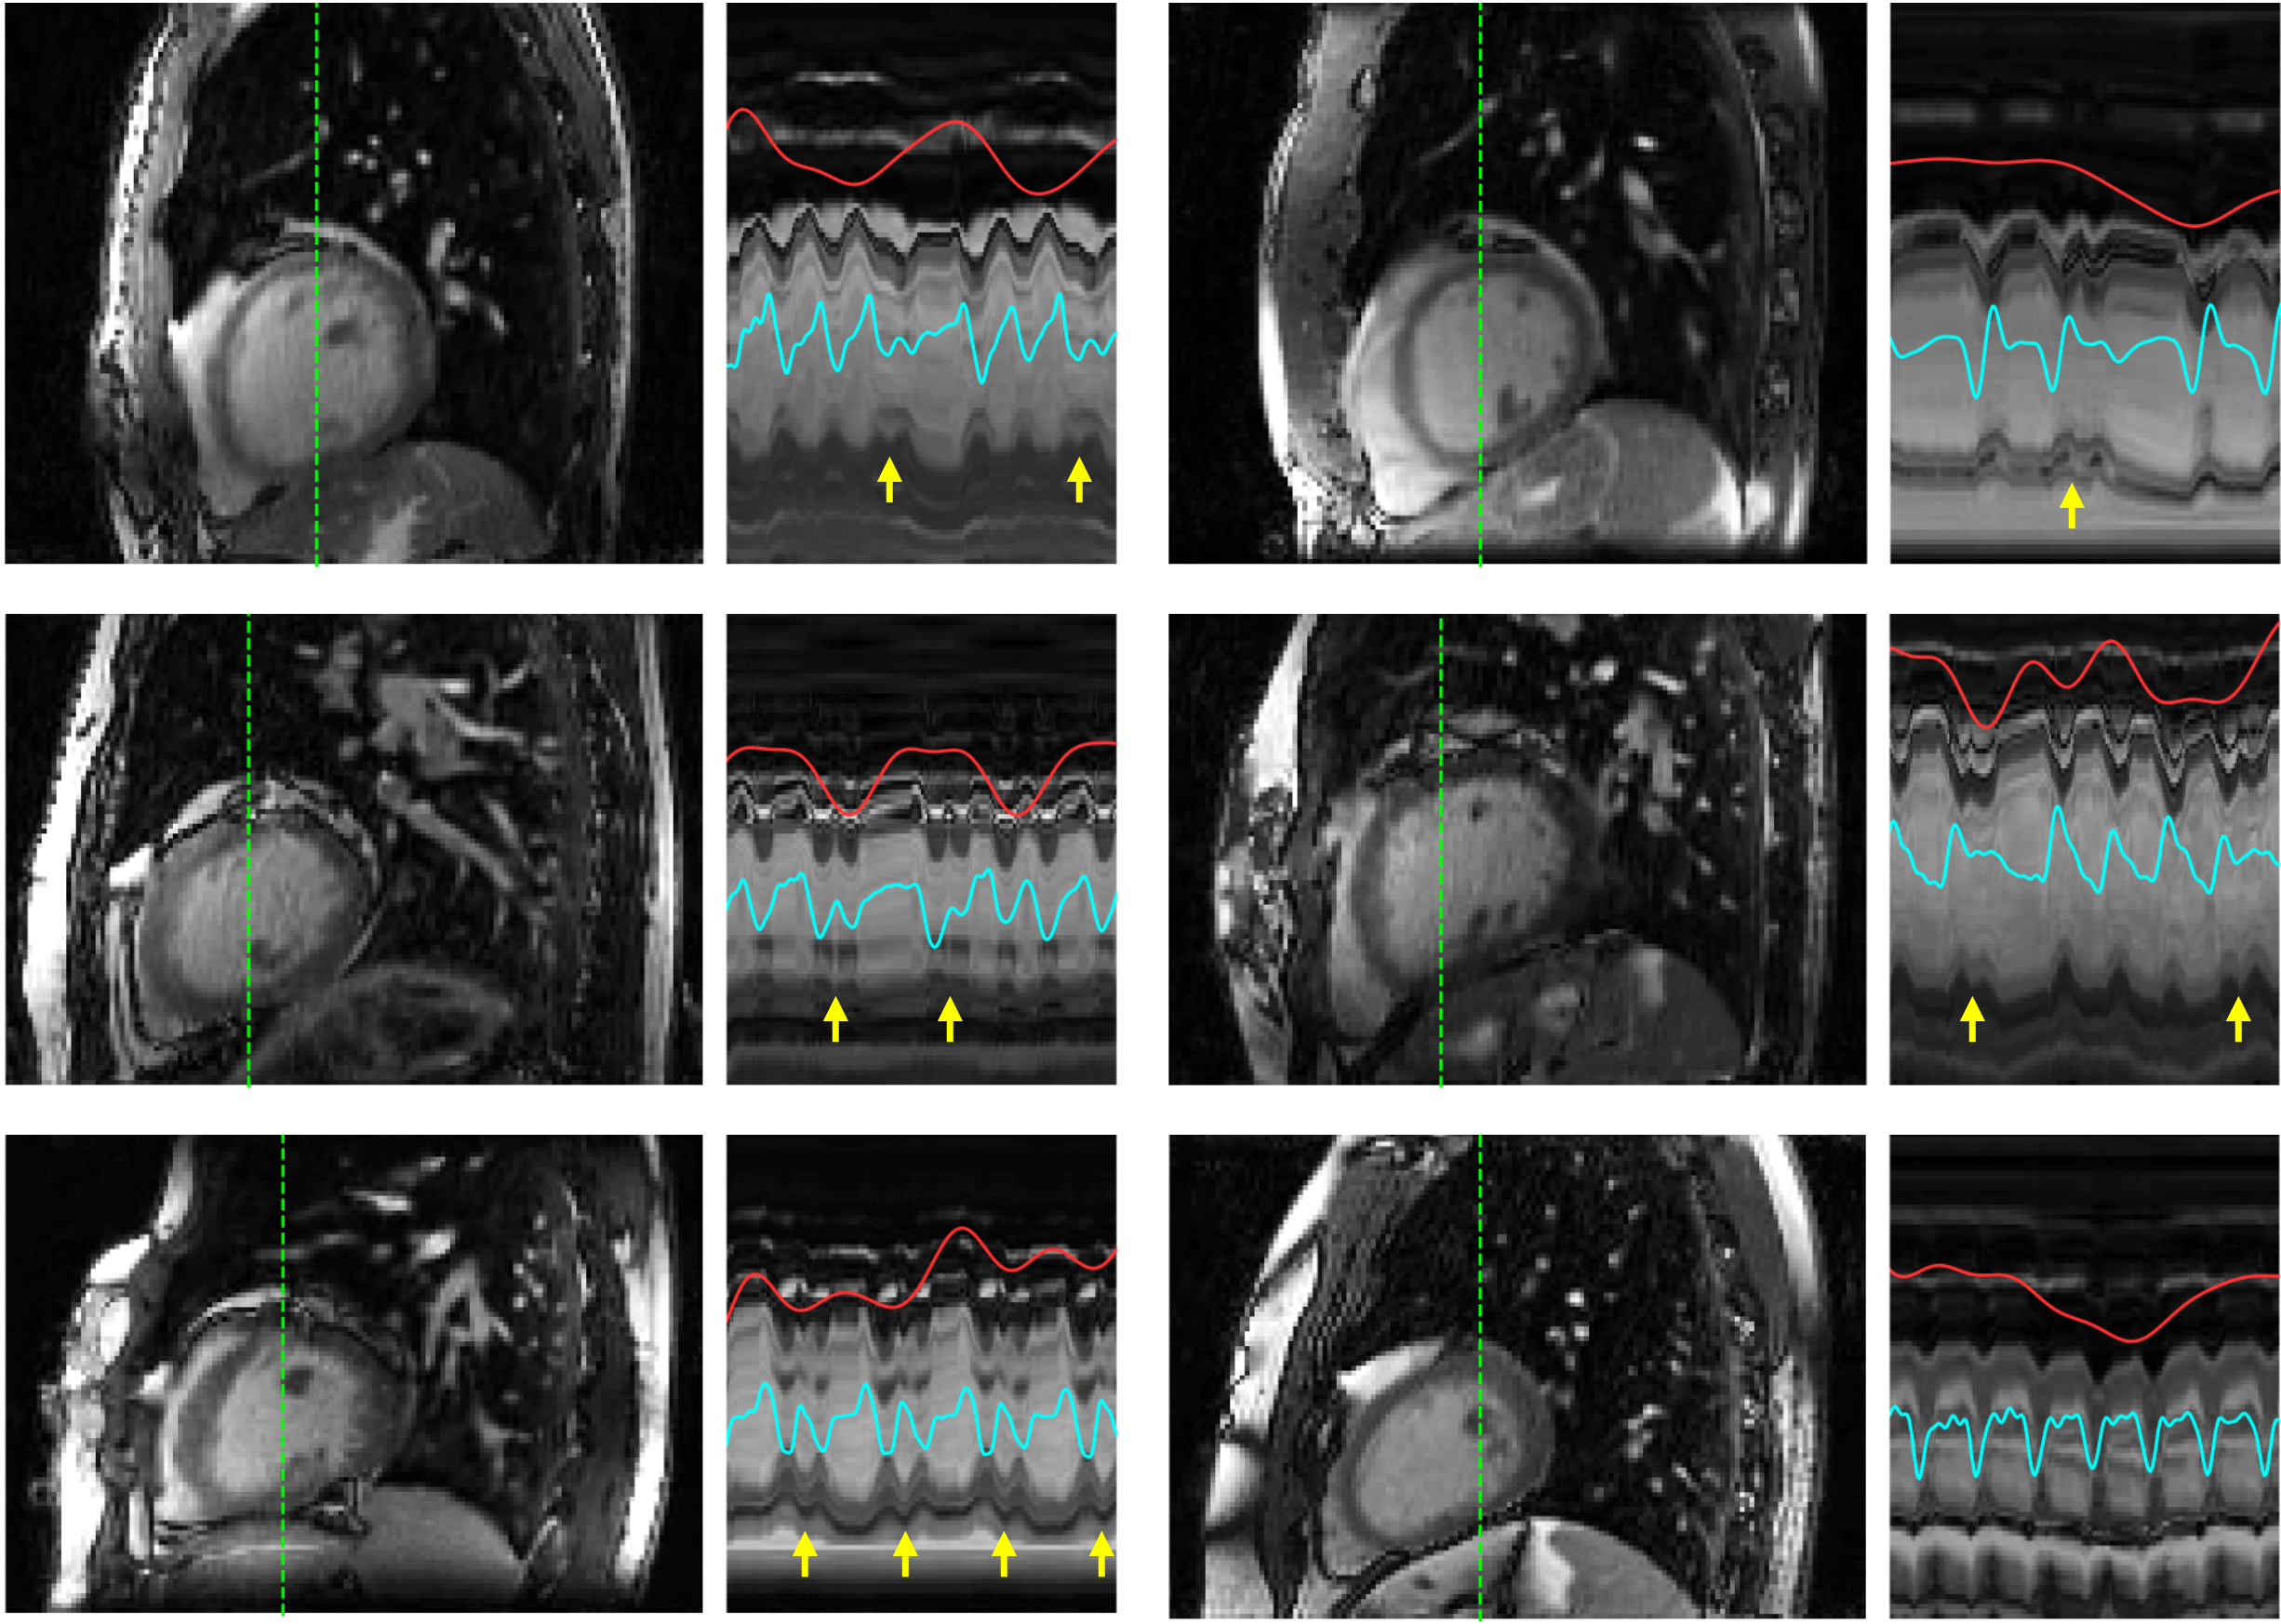

Figure 4 highlights the advantage of using a frame-specific composite image in ML-DIP. Relying on a single fixed template resulted in visible image distortions, as highlighted by the yellow arrows. Because the fixed-template approach performed poorly compared to ML-DIP, it was excluded from further comparisons. Figure 5 shows representative ML-DIP reconstructions from eight healthy volunteers scanned at rest. The corresponding x-t profiles highlight that ML-DIP preserves both cardiac and respiratory motions, closely following the self-gating signals. Figure 6 shows results from two additional volunteers scanned both at rest and during in-magnet exercise. During exercise, faster heart rates and exaggerated breathing patterns were captured without visible degradation in image quality. Figure 7 shows representative results from six of the 12 PVC patients. Despite lower blood–myocardium contrast, ML-DIP successfully captured beat-to-beat variations, including the timing and morphology of PVCs. PVC beats were easily identified on the reconstructed x–t profiles and corroborated by the self-gating signals.

In healthy subjects, blind scoring by cardiologists consistently yielded higher scores for ML-DIP, as summarized in Table 4. The advantage of ML-DIP over 5D-Cine was more pronounced during exercise, where 5D-Cine exhibited visible motion artifacts due to unaccounted torso movement. In PVC patients, where ferumoxytol was not used, 2D real-time scored higher than ML-DIP, which can be attributed to lower contrast in 3D imaging from blood pool saturation [33]. Nonetheless, ML-DIP received an average score of 4.50, with the lowest score of 3.75 for PVC #3. Despite arrhythmia rejection, 5D-Cine performed poorly in PVC patients, with eight subjects scoring below 3.00 and four scoring below 2.00. Only four PVC patients—three without arrhythmia during acquisition and one in stable bigeminy—received a score of 3.00 or higher. Figure 8 shows some of the short-axis images scored by expert readers. In healthy subjects, ML-DIP produced sharp, motion-artifact-free images, even during exercise. In PVC patients, ML-DIP reconstructed PVC beats, including the compensatory pauses following PVCs in one subject and alternating premature beats consistent with bigeminy in another. Beat-to-beat variations observed with ML-DIP were also consistent with the ECG traces, which are superimposed on the temporal profiles of the two PVC subjects in Figure 8. In contrast, 5D-Cine not only removed beat-to-beat variations but also exhibited extensive motion artifacts and blurring due to inconsistent cardiac binning. A movie, Video S2, corresponding to Figure 8, is shown in the Supplementary material. To highlight the improvement in blood-myocardium contrast from ferumoxytol, Video S3 in the Supplementary material presents two ML-DIP cine series: one from a healthy subject scanned with ferumoxytol at 3T and the other from a PVC patient scanned post-gadolinium at 1.5T.

Figure 7: Representative ML-DIP images in sagittal orientation from six out of twelve PVC patients. Space-time (x-t) profiles along the dashed green lines are shown to the right of the images. Each x–t profile spans 200 frames (6.6 s). The red and cyan curves represent self-gating-based respiratory and cardiac signals, respectively. PVC beats are indicated by yellow arrows. The compensatory pause is also visible after some of the PVC beats. One of the patients (bottom-left) was in bigeminy, evident in the x–t profile, and another patient (bottom-right) did not experience PVCs during the scan.

Figure 8: Representative short-axis images from 5D-Cine, 2D real-time, and ML-DIP for a healthy subject at rest, a healthy subject during exercise, and two patients. Space-time (x-t) profiles along the dashed green lines are shown to the right of the images. The ML-DIP x–t profiles span 200 frames (6.6 s), while the x-t profiles span 3 to 6 seconds for 2D real-time cine and one cardiac cycle for 5D-Cine. The 3D reconstructions from 5D-Cine and ML-DIP were interpolated along the 2D plane defined by the 2D real-time acquisition. Yellow traces show the ECG signal that was synchronously collected with the 3D acquisition. R-waves from sinus and PVC beats are marked with ‘*’ and ‘**,’ respectively. The yellow arrows indicate PVCs seen on the cine images. Artifacts due to uncompensated motion are observed in 5D-Cine, especially in the second, third, and fourth rows. Because 2D and 3D scans were performed separately, minor shifts in subject position are seen in some cases.